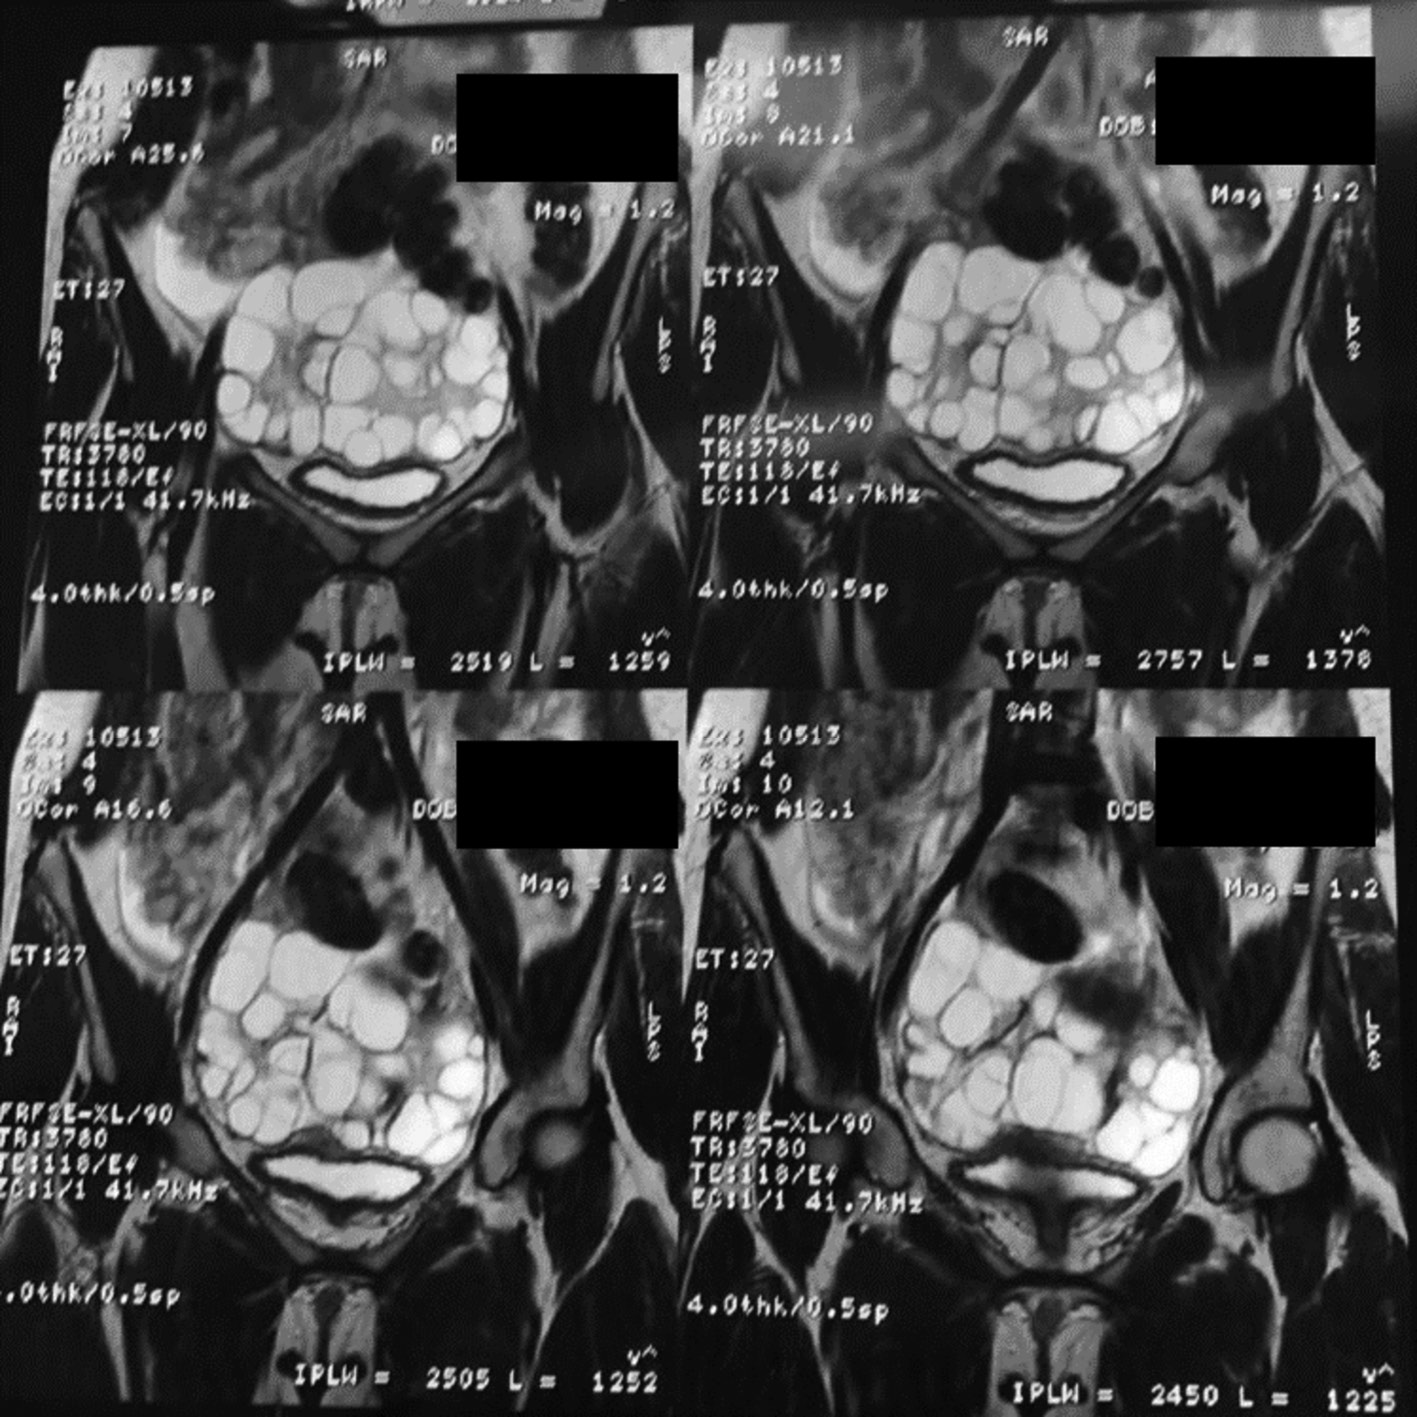

Пациентка была осмотрена офтальмологом, снижения остроты зрения не выявлено. По данным МРТ малого таза без контрастирования выявлены значительно увеличенные яичники (размеры не указаны) с множественными кистами, а также кзади от мочевого пузыря и уретры – кистозное образование неправильной формы 73×41×28 мм, заполненное однородным жидкостным содержимым (рис. 2).

Рис. 2. МР-изображение органов малого таза пациентки. Видны поликистозные увеличенные яичники.